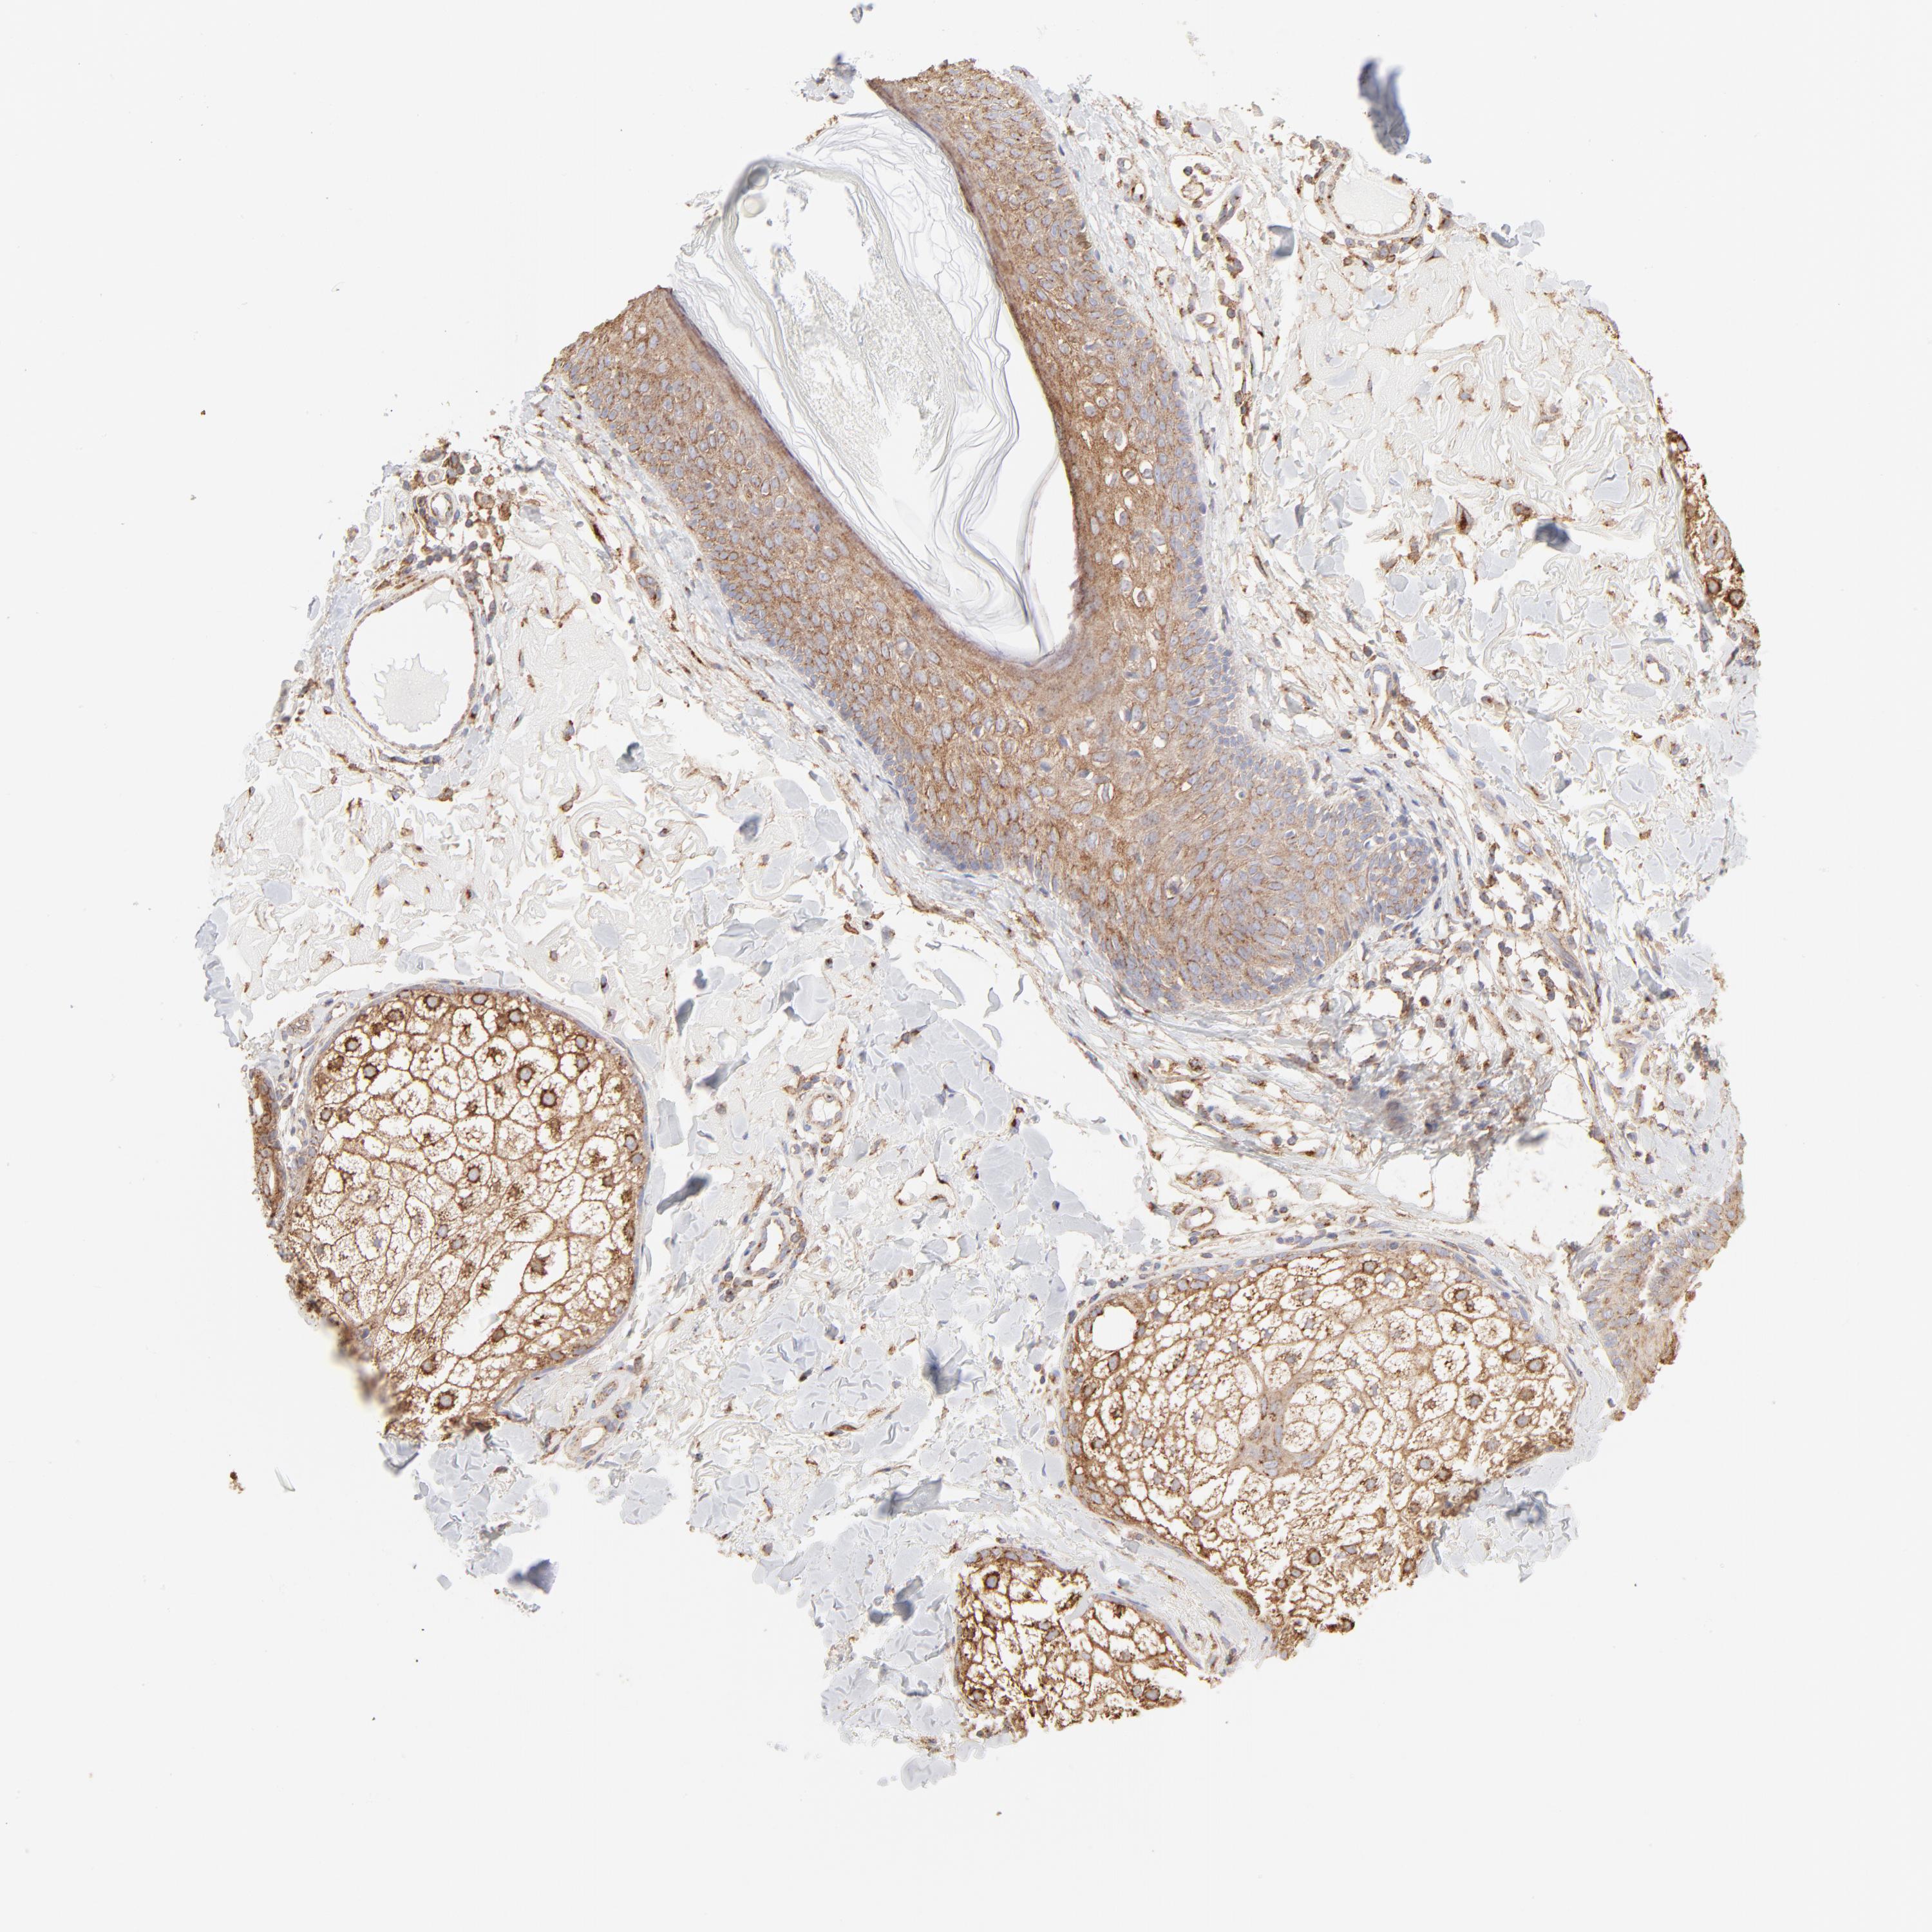

Basal cell and squamous cell cancer

SKIN CANCER - Protein expressioni

A mouse-over function shows sample information and annotation data. Click on an image to view it in a full screen mode. Samples can be filtered based on level of antibody staining by selecting one or several of the following categories: high, medium, low and not detected. The assay and annotation is described here.

Antibody stainingi

Antibody staining in the annotated cell types in the current human tissue is reported as not detected, low, medium, or high, based on conventional immunohistochemistry profiling in selected tissues. This score is based on the combination of the staining intensity and fraction of stained cells.

Each image is clickable and will lead to virtual microscopy that enables deeper exploration of all samples and also displays staining intensity scores, fraction scores and subcellular localization as well as patient and tissue information for each sample.

Antibody CAB003692

Staining

High

Strong

Moderate

Quantity

>75%

Location

Cytoplasmic/membranous

Squamous cell carcinoma, NOS